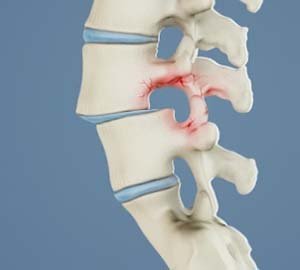

Spine Trauma or Fracture